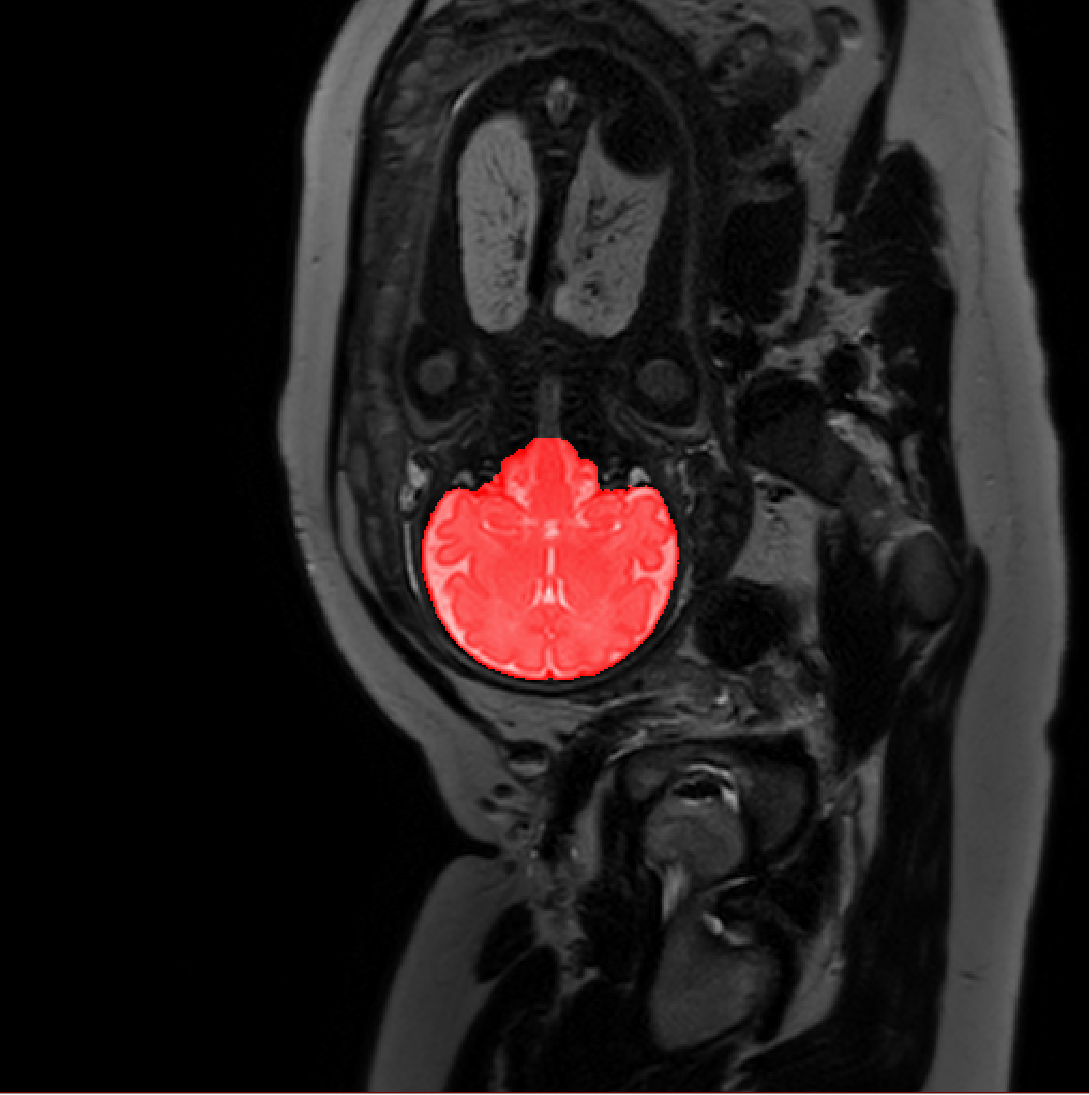

Table 1 lists average of quantitative evaluation results of these experiments and Figure 2 shows results obtained from each image. Figure 3 shows examples of the obtained segmentations.

Refer to caption

Figure 3: Example of ICV segmentations in images acquired in axial (left), coronal (middle) and sagittal (right) planes. Top row: A slice from T2-weigted image; Second row: Automatic segmentations obtained using 7 training images from the representative imaging planes; Third row: Automatic segmentations obtained using all 21 training images from all 3 image orientations; Bottom row: Manual segmentation.